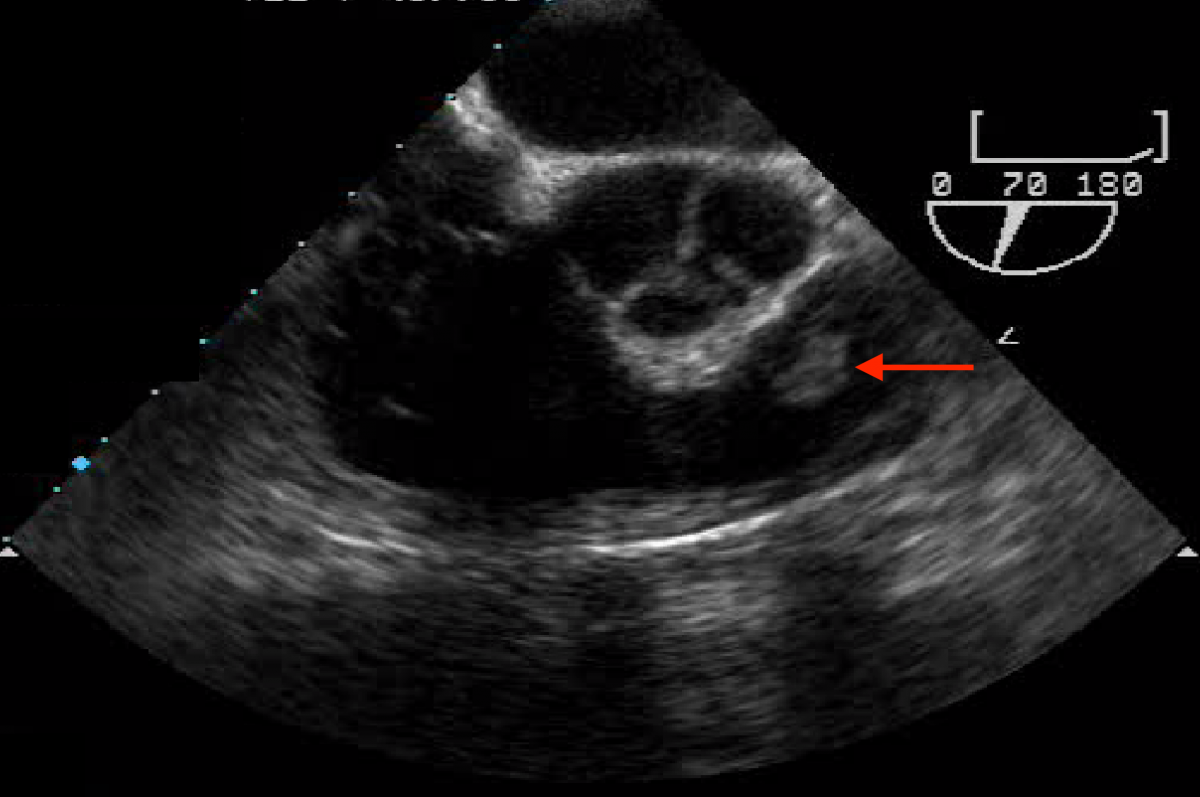

A 56-year-old Caucasian male presented with exertional dyspnea, occasional palpitations, and night sweats. He underwent transthoracic echocardiography, which suggested a possible pulmonic valve tumor. A follow-up transesophageal echocardiography demonstrated a freely mobile, well circumscribed, nearly 1 cm tumor on the anterior leaflet of an otherwise structurally normal pulmonic valve (Figure 1). Contrast chest CT was remarkable for bilobulated tumor of the pulmonic valve consistent with a PFE (Figure 2).